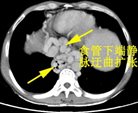

患者朱XX,男,49岁,因“上腹部胀痛2天”2015年入院,查体:脾脏肋下15cm。入院时血液学检查:白细胞明显降低仅为0.8X109/L,血小板明显降低仅为 23X109/L。入院时彩超:脾大Ⅲ度,门静脉、脾静脉内异常回声(考虑血栓形成),腹腔积液。

入院CT

临床诊断:肝硬化、门静脉高压 门静脉、脾静脉血栓 脾功能亢进 食管、胃底静脉曲张(重度)门脉高压性胃病